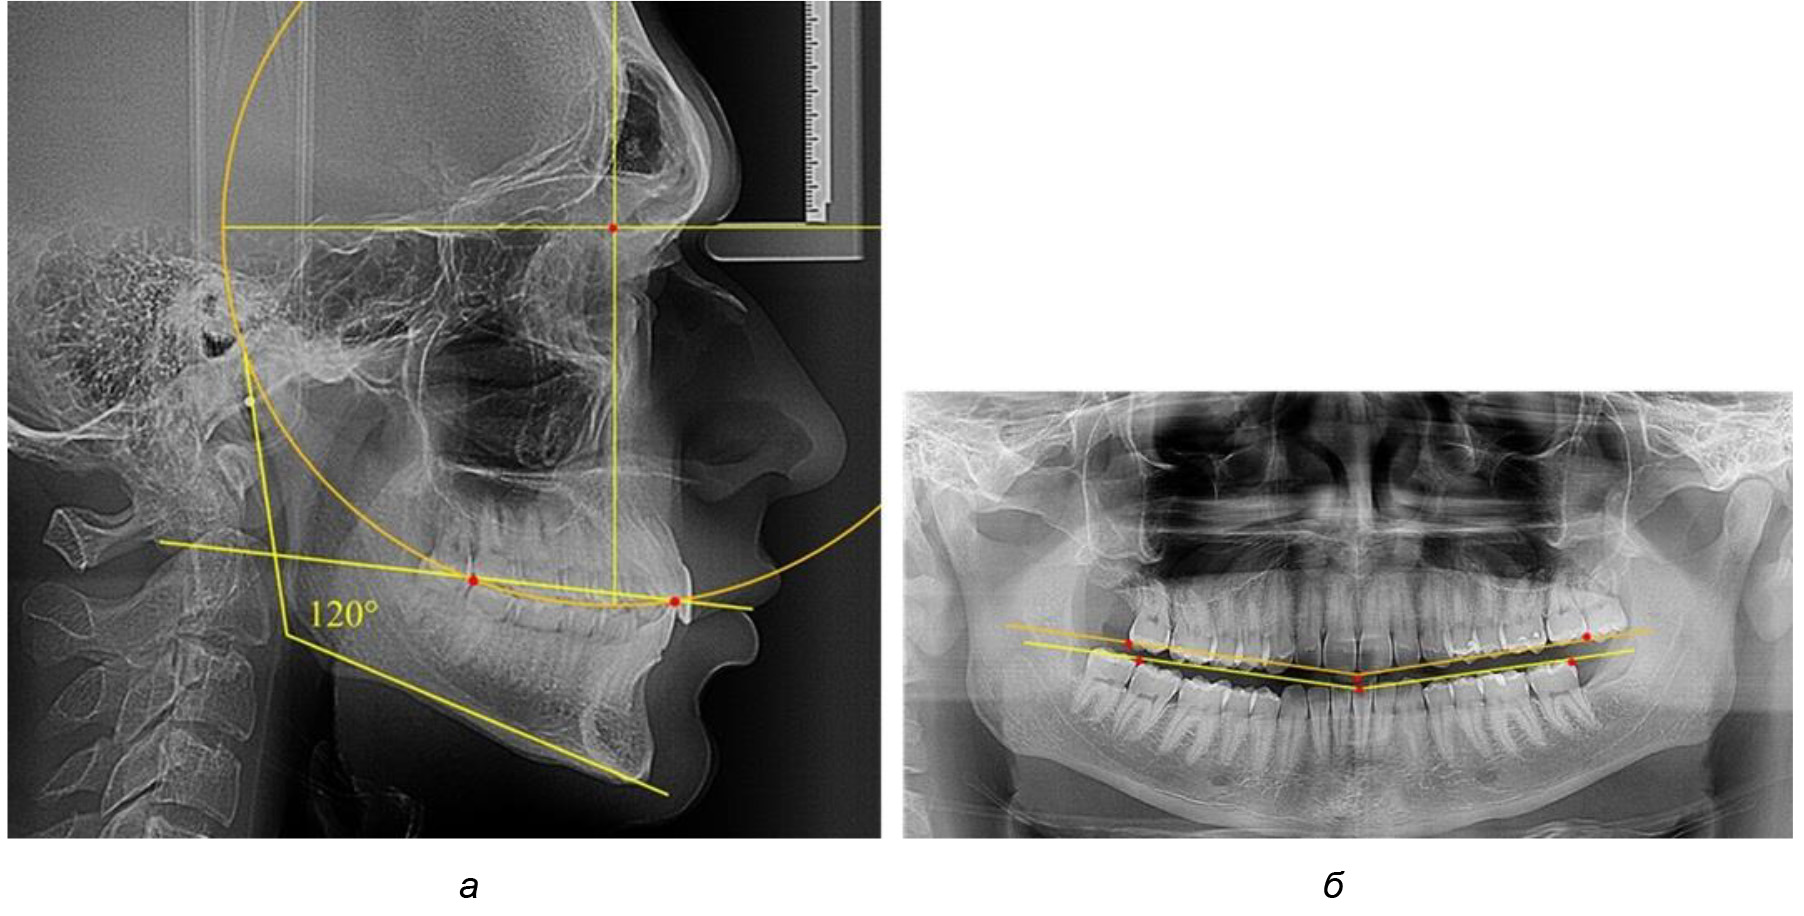

При анализе латеральных ТРГ устанавливали реперный окклюзионные точки в переднем и боковом отделе. Передняя точка устанавливалась на режущем крае нижнего медиального резца, которую в клинике ортодонтии обозначают как vPOcP. Дистальная точка второго нижнего моляра обозначалась как hPOcP. Измеряли расстояние между окклюзионными точками, что определяло сагиттальный размер окклюзионной линии. Использование программ PowerPoint позволило проводить окружность, проходящую по линии смыкания зубов через окклюзионные точки. Измеряли радиус окружности. Учитывая вариабельность размеров окклюзионной линии и радиуса окружности, определяли относительный показатель через отношение радиуса круга к длине сагиттального размера окклюзионной линии. Глубину окклюзионной кривой измеряли от точки наибольшей выпуклости до окклюзионной линии (рис. 1). На ортопантомограмме (ОПТГ) также соединяли окклюзионные точки правой и левой стороны и измеряли глубину окклюзионной кривой от точки наибольшей выпуклости до окклюзионной прямой линии. Результаты глубины кривой Spee сравнивали по данным ТРГ и ОПТГ.

Рис. 1. Метод определения кривой Spee на ТРГ (а) и на ОПТГ (б)

Анализ результатов показал, что глубина кривой Spee в среднем по подгруппе составил (4,12 ± 0,53) мм как при анализе ТРГ, так и ОПТГ.

Деление величины радиуса круга к длине окклюзионной линии составило 1,623 ± 0,02. Таким образом, для определения радиуса окружности, соответствующей кривизне окклюзионного контура боковой ТРГ, необходимо измерить расстояние между передней и задней окклюзионными точками и последующим умножением полученной величины на число Фибоначчи (рис. 2).